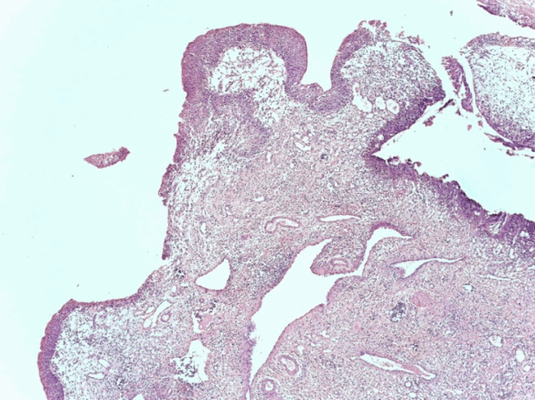

Патоморфологическая картина продемонстрирована на рисунке ниже.

Патоморфологическое исследование пациентка О.

Морфологическая картина полипоидного цистита с наличием гиперплазированного уротелия, признаков острого и хронического воспаления, реактивной уротелиальной атипии с множественными митозами, отеком собственной пластинки слизистой с фиброзом и полнокровными сосудами и полипоидными выпячиваниями. Окраска гематоксилин-эозином, х5